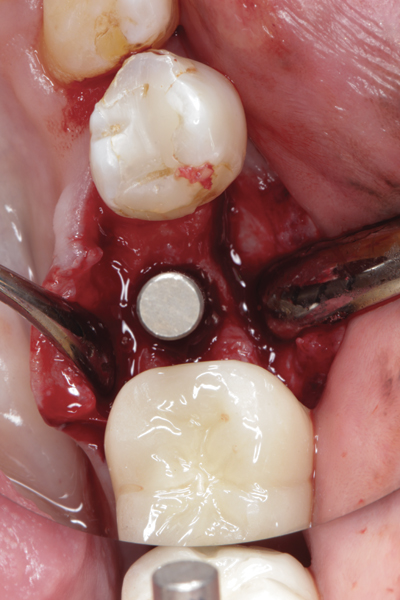

Fig 1. (Case 1) Tooth No. 19 manifested a buccal fistulous tract. Probing depth on the buccal was 8 mm.

Figure 1

Fig 11. An implant was placed in regenerated bone.

Figure 11

All three studies7-9 addressing defective alveolar ridges reported a positive finding with respect to healing, which facilitated implant placement in all monitored patients. In addition, the four cases presented by the current authors (Figure 1 through Figure 25) attained excellent results with d-PTFE plus an alloplastic bone graft (Puros) when treating buccal wall defects.

Case Presentations

The four presented cases shown in Figure 1 through Figure 25 were all treated in a similar manner as outlined in detail in the captions for the first case (Figure 1 through Figure 11). In all four cases, teeth with pathosis were removed, buccal and lingual flaps were elevated, and sites were surgically debrided. A Cytoplast d-PTFE barrier was sized and inserted usually under the buccal flap, the bone graft was added, the barrier was then tucked under the lingual flap, and the flaps were sutured. Bone grafts were used in all of the cases, because buccal bony plates were resorbed and the bone graft helped support the barrier.